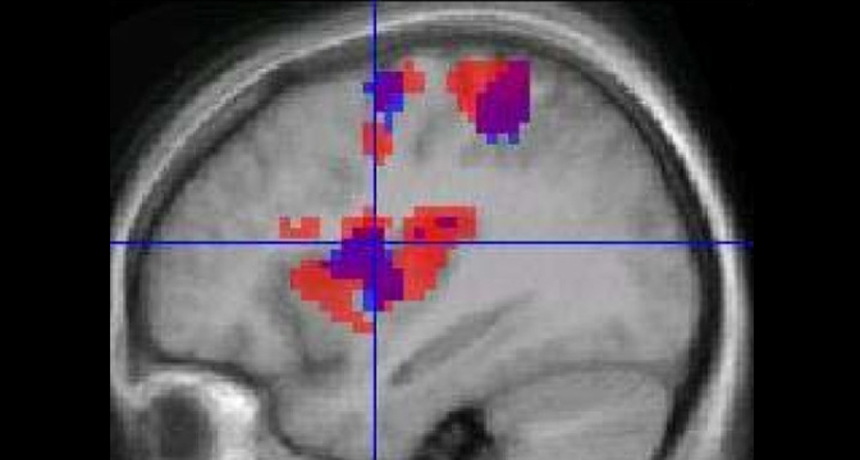

GO WITH THE FLOW  Functional MRI scans use blood flow (colors represent changes in blood flow) to indicate nerve cell behavior, but those two things aren’t always coupled, a new study finds.

K. Roberts et al/BMC Anesthesiol. 2008/Open-I (CC BY 2.0)

A mainstay of many neuroscience labs, functional MRI relies on blood flow changes in the brain to serve as proxies for active nerve cells. But a new study on mice finds that neurons can be busy with no hint of blood-flow changes.

Functional MRI detects tiny changes in the brain’s amount of oxygenated blood, which researchers often interpret as signs of neurons sending off more electrical messages.  And in some cases, that interpretation is correct. But by finding a case when neurons are busy with no corresponding change in blood movement, the new study shows that blood flow isn’t always a reliable marker of neural activity. “The picture is getting more and more complicated,” Keilholz says.